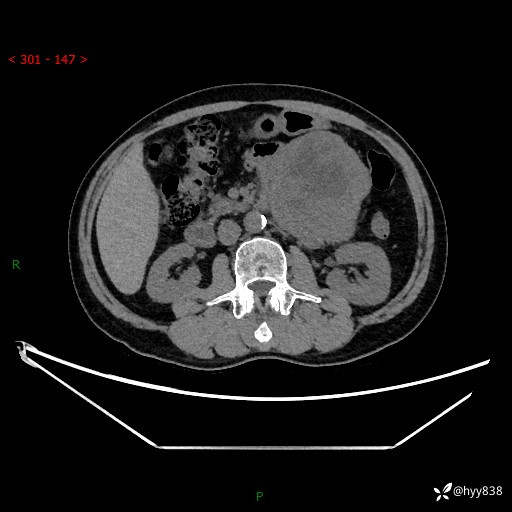

年龄:61岁

主诉:发现腹膜后肿瘤3天

腹部CT平扫+增强(动脉期+静脉期)